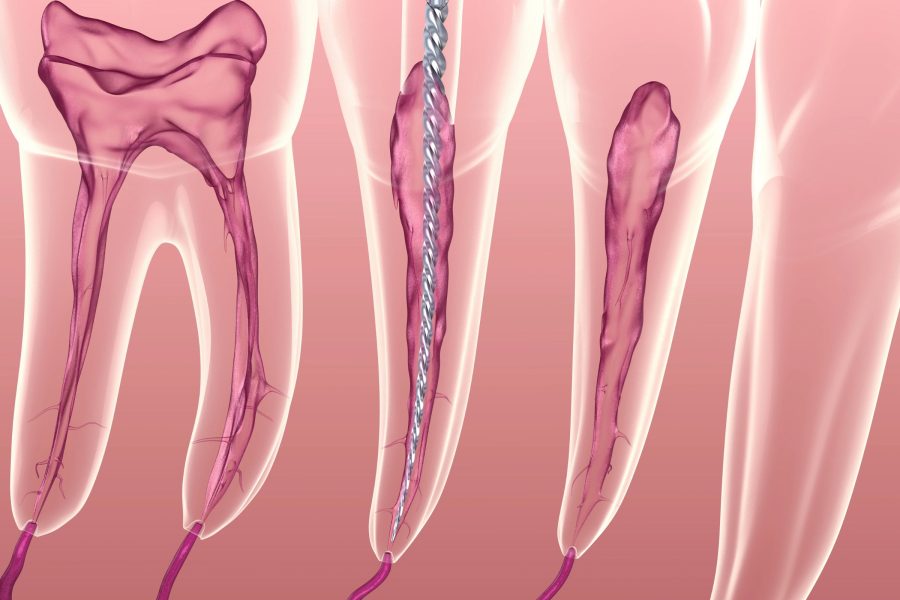

Tratamentul endodontic, cunoscut popular drept scoaterea nervului, este o procedură menită să salveze un dinte afectat de infecție sau inflamație ireversibilă a pulpei dentare. Scopul…